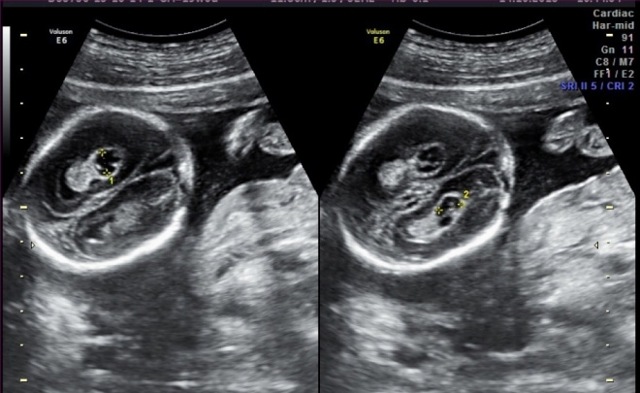

Сосудистые сплетения у плода образуются на сроке 18-19 недель. Именно в этот период, при проведении УЗИ могут быть обнаружены первые признаки кист, которые выглядят, как эхонегативные образования. Чаще всего в срок от 20 до 24 недель, когда идет активное формирование головного мозга, размер кисты уменьшается, и она полностью исчезает.

Статистика утверждает, что кисты сосудистого сплетения образуются в 1-2% случаев. Самопроизвольное их рассасывание происходит к 24-й неделе в 90% случаев. Размер их считается мелким до 5 мм.

Первые нарушения развития определяются ещё во внутриутробном периоде. Женщина проходит обязательные исследования. Благодаря ранним скринингам выявляют кисты сосудистых сплетений. Уже от 16 недель их можно контролировать с помощью повторной диагностики.

Проводится в период внутриутробного формирования. Это дает возможность установить наличие кистозной опухоли на начальных этапах ее формирования.

По неизвестным до сих пор причинам у некоторых эмбрионов возникает так называемая киста сосудистого сплетения головного мозга у плода. По факту это скопление жидкости в самом сплетении, которое выглядит на УЗИ как киста. Оно встречается с частотой от 1 до 3% всех случаев обследования беременных, иногда киста может быть односторонней или двусторонней, единичной или множественной.